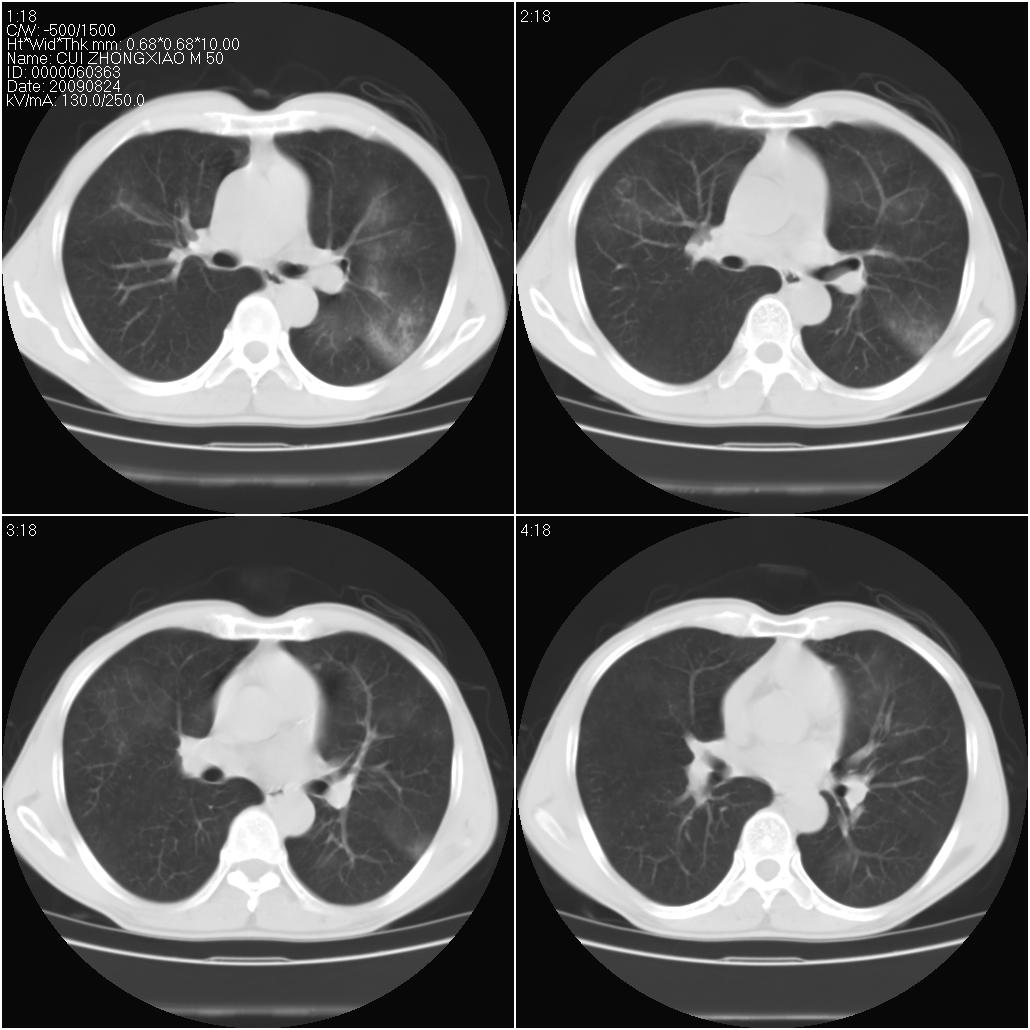

标题: CT21851:男性,50岁。间断性咳嗽半年。 [打印本页]

标题: CT21851:男性,50岁。间断性咳嗽半年。

磨玻璃样改变(左肺及右肺上叶前段),边缘模糊,考虑炎症,建议严格抗炎治疗后复查除外肺泡蛋白沉积症或肺泡出血(病人有咯血吗) 肺泡癌.

肝左叶肝内胆管扩张,进一步检查.

双肺磨玻璃征改变。。。支持楼上

考虑以感染性病变,以结核可能性大,建议治疗后复查。